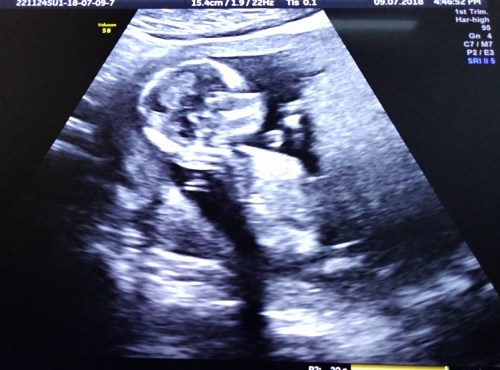

2018.07.09 My first ultrasound view of Peanut, my grandson

2018.07.09 My first ultrasound view of Peanut